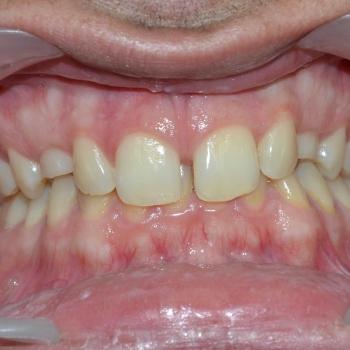

Ádám és édesanyja fogorvosuk javaslatára kerestek fel a felső állcsontban rekedt maradó szemfogak sorbaállításának kérésével. A panoráma röntgenfelvétel elemzése alapján egyértelművé vált, hogy a maradó szemfogak hibás tengelyállása okozta a tej szemfogak perzisztenciáját és a maradó szemfogak előtörésének a hiányát. A szemfogak 30 és 45 fokos dőlésének klinikai képet tovább árnyalták egyéb fogszabályozási eltérések is, mint például a mélyharapás, a nagymetszők közötti rés, illetve jobb oldali második nagyőrlők közötti fordított keresztharapás.

Ádám kitartásának köszönhetően a kezelés végére minden maradó fog a helyére került és egy esztétikailag és funkcionálisan is tökéletes harapást kaptunk.